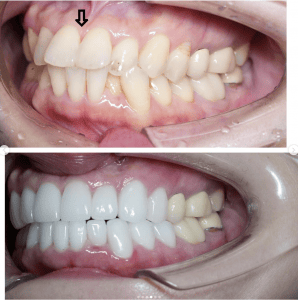

Case001 – セラミック矯正

「昔から歯並びが気になっているので治したいが、もうすぐ海外に行くので時間がない」

「可能な限り安く、できるだけ自分の歯は削らないで綺麗に見えるようにして欲しい」

という患者様の症例です。

【治療内容】

上4本下4本 オールセラミッククラウン

【治療期間】

1ヶ月

【治療費】

840,000円

担当:理事長 佐藤悠野

Before写真にある下顎の最も前に出ている前歯を矯正なしで治療するために、神経をとる必要があった